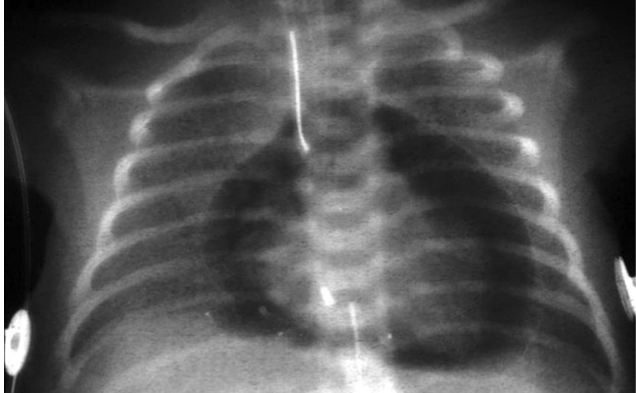

cardiac tamponade

Blows to the chest can lead to __________ caused by bleeding between the visceral and parietal pericardial membranes.

pericardial tamponade

If the heart is unable to pump blood properly, then the venous blood traveling towards the heart backs up. This will lead to

external jugular vein distention (JVD). One cause of JVD is cardiac tamponade.

A common treatment for cardiac tamponade is to

carefully insert a needle through the parietal pericardium and aspirate off some of the excess fluid to relieve the pressure on the outside of the heart.